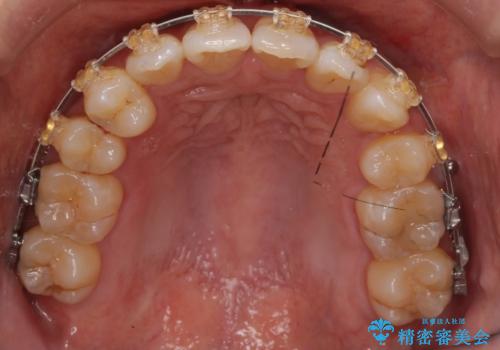

右上の犬歯が奥深く埋伏していました。

右上以外の3本を抜歯しきちんと並べました。